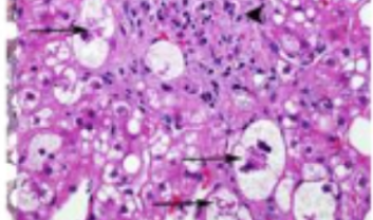

- Le Data Challenge ML-KIDCAR (IHU ICAN) vise à développer des modèles d’apprentissage profond capables de détecter la survenue d’insuffisance rénale aiguë après une chirurgie cardiaque, grâce à des données opératoires.